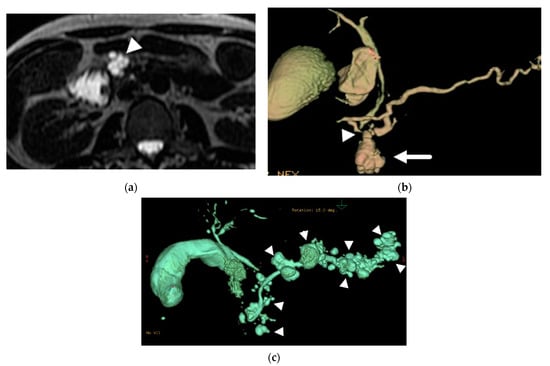

8.1. Use of Secretin